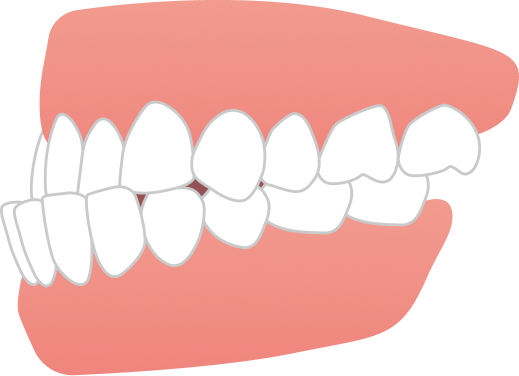

治療期間は1年3ヶ月で、前歯の位置関係と歯列のバランスを整えることで、気にされていた前歯の突出感が改善されました。

見た目の変化だけでなく、違和感の少ない治療経過にもご満足いただき、安心して矯正治療を進めていただくことができた症例です。

治療後にはご自身の笑顔がもっと好きになれた!と大変嬉しいご感想をお寄せいただきました。

AFTER